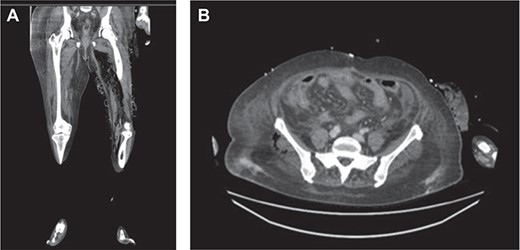

Within 14 hours postoperatively, she developed an erythematous patch on her left thigh, and a creatine kinase of 19 000. A bedside finger test was performed which showed dirty dishwater fluid, necrotic fat and lack of bleeding. She was taken to theatre for urgent debridement for suspected NF. Antibiotics were changed to Meropenem, Vancomycin, Lincomycin and Fluconazole. She had extensive debridement of the soft tissue circumferentially on the left thigh, including some muscle. In 10 hours postdebridement, there was a radiological evidence of disease progression with gas in muscle compartments on the lower limb X-rays (Fig. 2a and b), and CT abdomen and lower limbs demonstrating gas throughout the whole left leg and a non-contiguous area in the right gluteal region (Fig. 3a and b). A diagnosis of multi-focal non-contiguous necrotising myositis was made.

(a) Air in the deep medial and posterior compartments of the thighs and calf suggestive of residual infection in the deep compartment. (b) New finding of air in the right gluteus medius muscle.